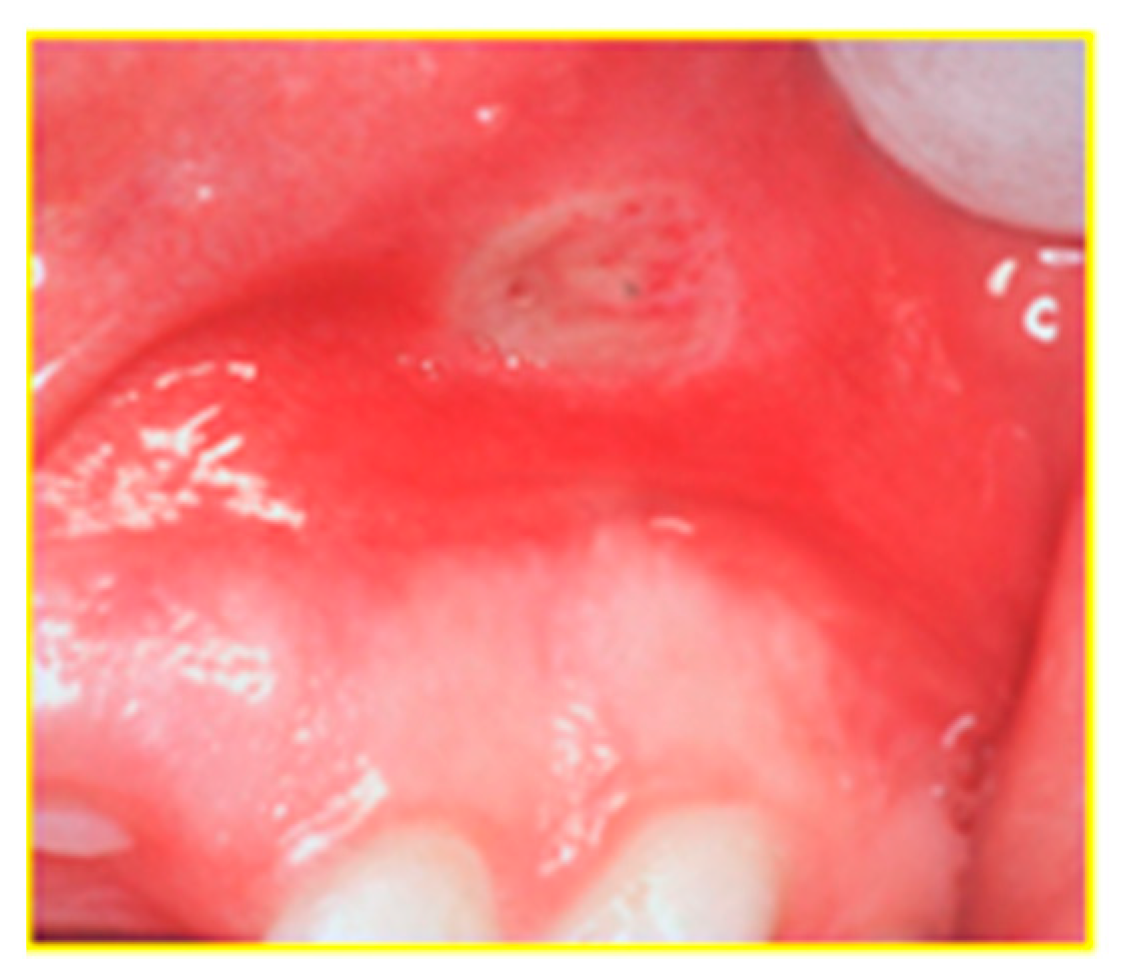

| Specific manifestations | Oral manifestations | Crohn’s disease | Ulcerative colitis |

| Cobblestoning the mucosa | X | ||

| Granulomatous cheilitis | X | ||

| Mucosal tags | X | ||

| Pyostomatitis vegetans | X | ||

| Unspecific manifestations | Deep oral fissuring | X | |

| Cheilitis angularis | X | X | |

| Dental caries | X | X | |

| Mucogingivitis | X | X | |

| Periodontitis | X | X | |

| Lichen planus | X | X | |

| Dysphagia | X | X | |

| Dry mouth | X | X | |

| Halitosis | X | X | |

| Taste changes | X | X | |

| Aphthous ulcerations | X | X |